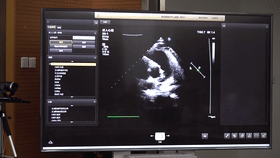

5G遠(yuǎn)程會(huì)診現(xiàn)場,西安國際醫(yī)學(xué)中心心內(nèi)科張衛(wèi)澤主任、超聲科陳姍姍主任打開4K高清顯示器,屏幕上立刻出現(xiàn)了商洛國際醫(yī)學(xué)中心的B超畫面,一位醫(yī)生正在為患者做心臟B超,隨著探頭的轉(zhuǎn)動(dòng),超聲機(jī)器上的畫面清晰可見,雖然兩家醫(yī)院相距一百多公里,但畫面流暢,沒一點(diǎn)拖沓。

“真的太棒了”張衛(wèi)澤表示,“沒有延時(shí)與卡頓,清晰的好像在一個(gè)房間內(nèi)進(jìn)行病歷討論”。陳姍姍非常興奮,直呼很震撼。她告訴筆者,“以前做遠(yuǎn)程會(huì)診,經(jīng)常遇到畫面和聲音不在一個(gè)頻道、畫面模糊等情況,遇到疑難病歷只能將影像拷下來回去研究,現(xiàn)在好了這些問題都將一次性解決?!?/span>